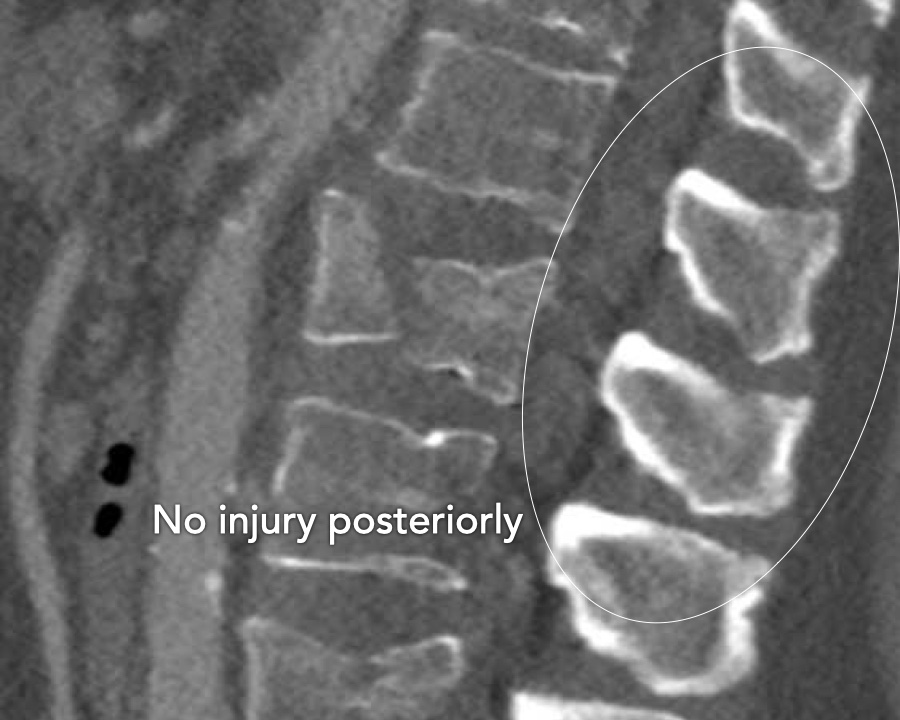

A2 Split fracture

A2 is a fracture of both endplates without involvement of the posterior wall of the vertebral body.

What is the highest AO-type of injury?

Findings:

- No C or B injury

- Fracture of the vertebral body with involvement of both endplates (1+1 points), no posterior wall involvement

Conclusion

injury type A2